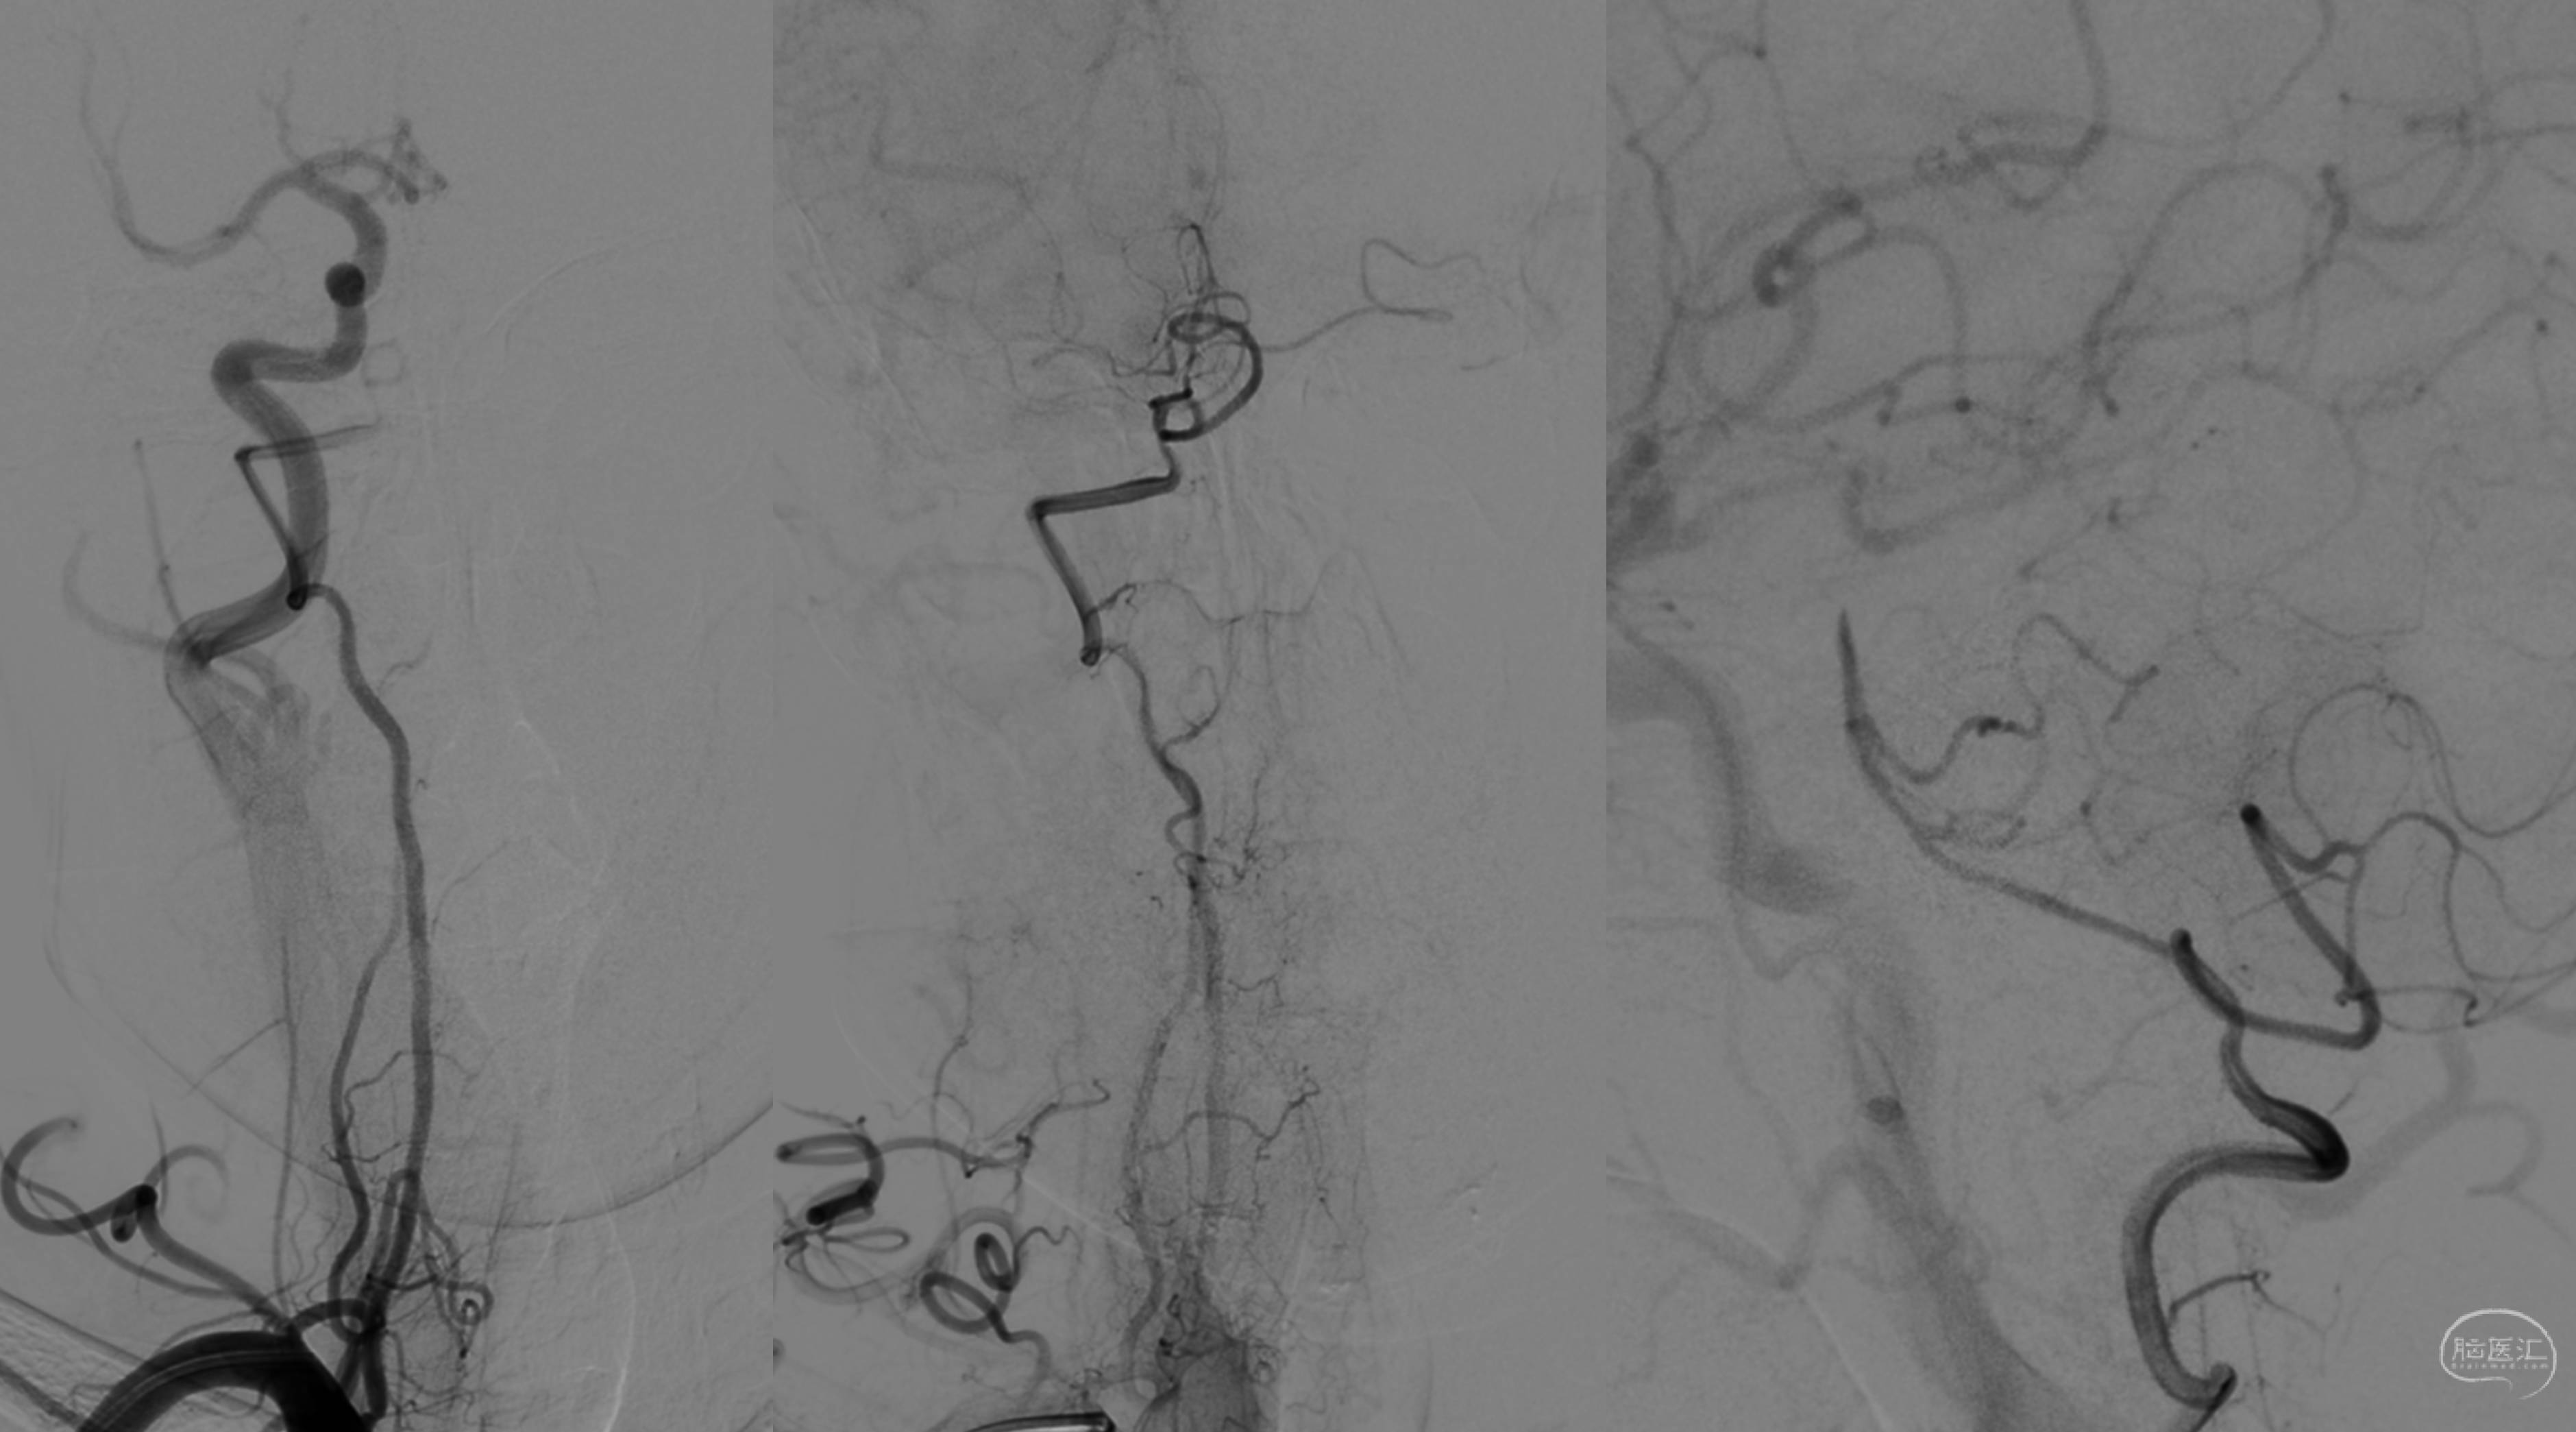

Step4,V3暴露!再次明确椎动脉沟后,基本了解椎动脉位置。再利用组织剪锐性分离枕下三角内的脂肪组织,暴露深部椎动脉及椎旁静脉丛!在椎旁的静脉丛完整呈现出来的时候,发自内心的赞叹造物主的伟大,于细微处现绝妙之美景。现仍能回味当时的心境,就如同夏日炎炎之时获得了一串美味的葡萄!当然,再美之物还是得抛开,因为深藏其中的椎动脉,才是终极宝藏!电凝后剪开,暴露椎动脉V3段,备用!(术中在暴露后进行了ICG造影,证实V3管腔通畅,不需要备用方案进行开颅)

Step 5,OA-V3 bypass。枕动脉标准的外膜修剪,鱼嘴样成形。引入术野。椎动脉临时阻断,切开。端侧吻合......其实这一段的工作倒是不难,毕竟血管粗大,管壁结实,8-0的缝合线缝起来扎实有力!吻合完成后,ICG造影确认通畅 。